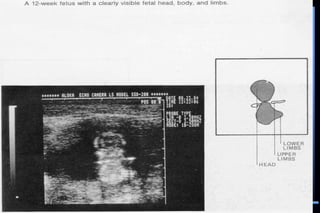

 Crown rump length (CRL)

Ultrasonic Landmark Occurence

(weeks of gestation)

 Gestational sac 5 – 6 weeks

 Fetal embryonic pale 6 – 7 weeks

 Detection of fetal life 7 – 8 weeks

 Placenta 8 – 10 weeks

 Loss of gestational sac 11 – 13 weeks

 Fetal head 11 – 14 weeks

(Biparietal diameter)